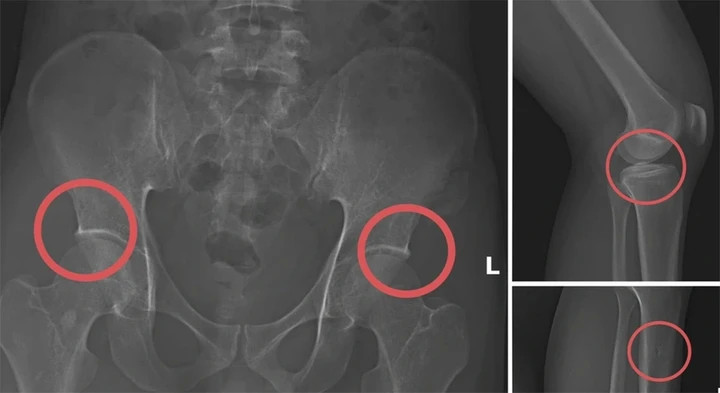

Một số tổn thương xương được Tạ Minh Châu tạo ra nhằm trục lợi bảo hiểm nhân thọ